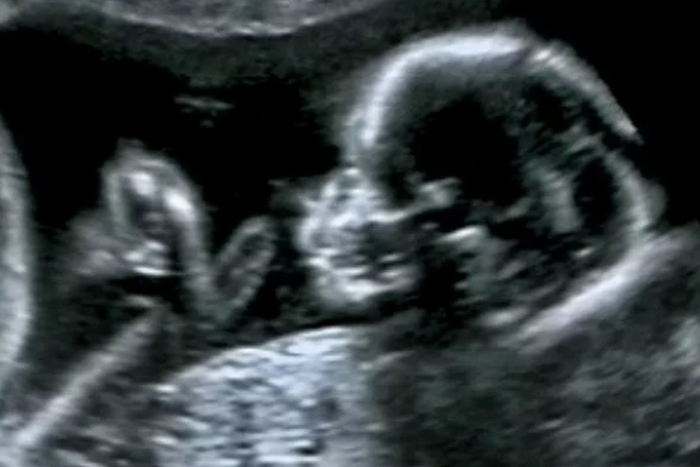

Pregnancy tests strips are excellent for confirming pregnancies in the early stages. The strips are used in conjunction with a person’s urine to check for the level of the human Chorionic Gonadotropin (hCG). You can confirm a pregnancy as early as two weeks after fertilization.